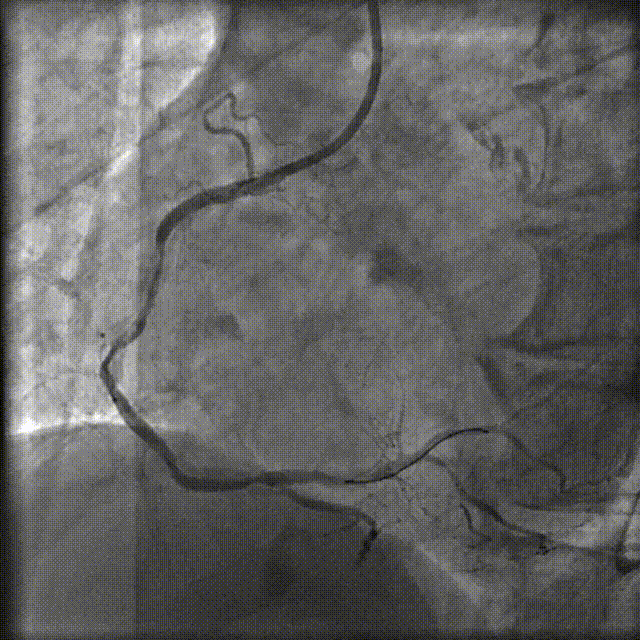

PCI过程-冲击波球囊PTCA

沿导丝送3.0×12mmGennWave冲击波球囊至RCA严重钙化病变处,充盈1:1比例造影剂盐水,以4atm低压扩张,每周期给予10秒、每秒1次血管内冲击波治疗后扩张至6atm,共进行8周期血管内冲击波治疗。

PCI过程-再次冲击波球囊PTCA

沿导丝送3.5×12mmGennWave冲击波球囊至RCA严重钙化病变处,充盈1:1比例造影剂盐水,以4atm低压扩张,每周期给予10秒、每秒1次血管内冲击波治疗后扩张至6atm,共进行8周期血管内冲击波治疗。